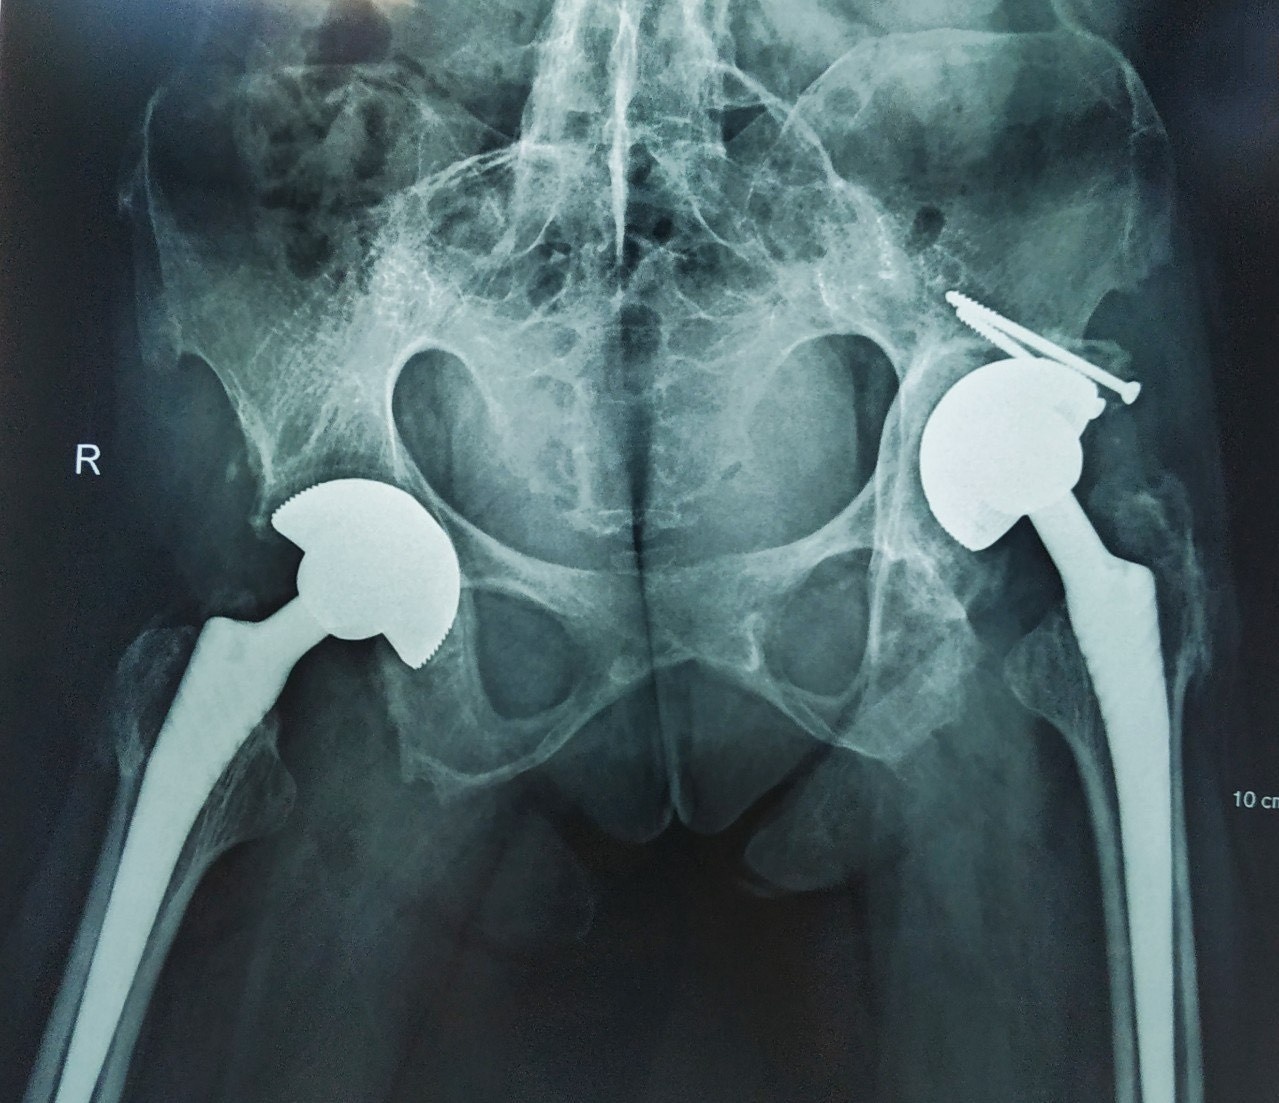

Hình ảnh X-quang của bệnh nhân bị viêm cột sống dính khớp. Ảnh: BVCC.

Tiến sĩ, bác sĩ Ngô Bá Toàn, Phó trưởng khoa Phẫu thuật Chấn thương chung, người trực tiếp phẫu thuật, cho biết ca mổ này rất phức tạp, cả 2 khớp kháng của bệnh nhân đã biến chứng viêm dính biến dạng.

Hiện các bác sĩ không có cách điều trị triệt để viêm cột sống dính khớp. Các phương pháp điều trị chỉ có thể cải thiện triệu chứng và ngăn bệnh trở nên xấu đi. Phẫu thuật thay khớp háng được chỉ định trong trường hợp bệnh nhân đau kéo dài, hạn chế vận động và có phá hủy cấu trúc rõ trên hình ảnh X-quang. Trong khi đó, phẫu thuật chỉnh hình đối với cột sống được chỉ định khi cột sống biến dạng.